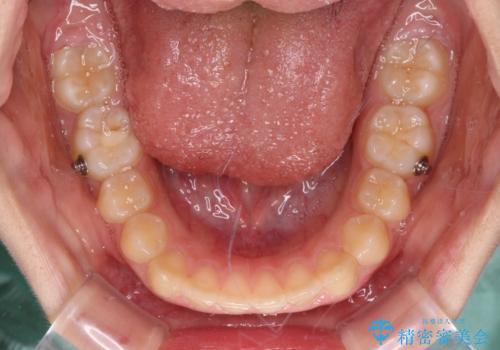

- ヨーロッパにてインビザライン矯正を始めたものの、日本に転居することになり、治療の継続を希望して来院された患者様です。

治療計画に無理がなく、現地担当医と速やかに連絡が取れるとのことで、インビザライン社での転医手続きを行い、継続して治療を行うこととしました。

舌の突出癖により、上下前歯が非接触となっていたため、トレーニングを徹底的に指導し、安定した咬み合わせにより終了させることができました。